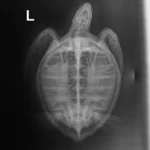

3.3 lbs juvenile green

Minor abrasions on the carapace, plastron, chin and flippers

In-house PCV = 31%, TP = 3.0 g/dl, glucose = 109. Started on Ceftaz, Vitamin B, and Normosol